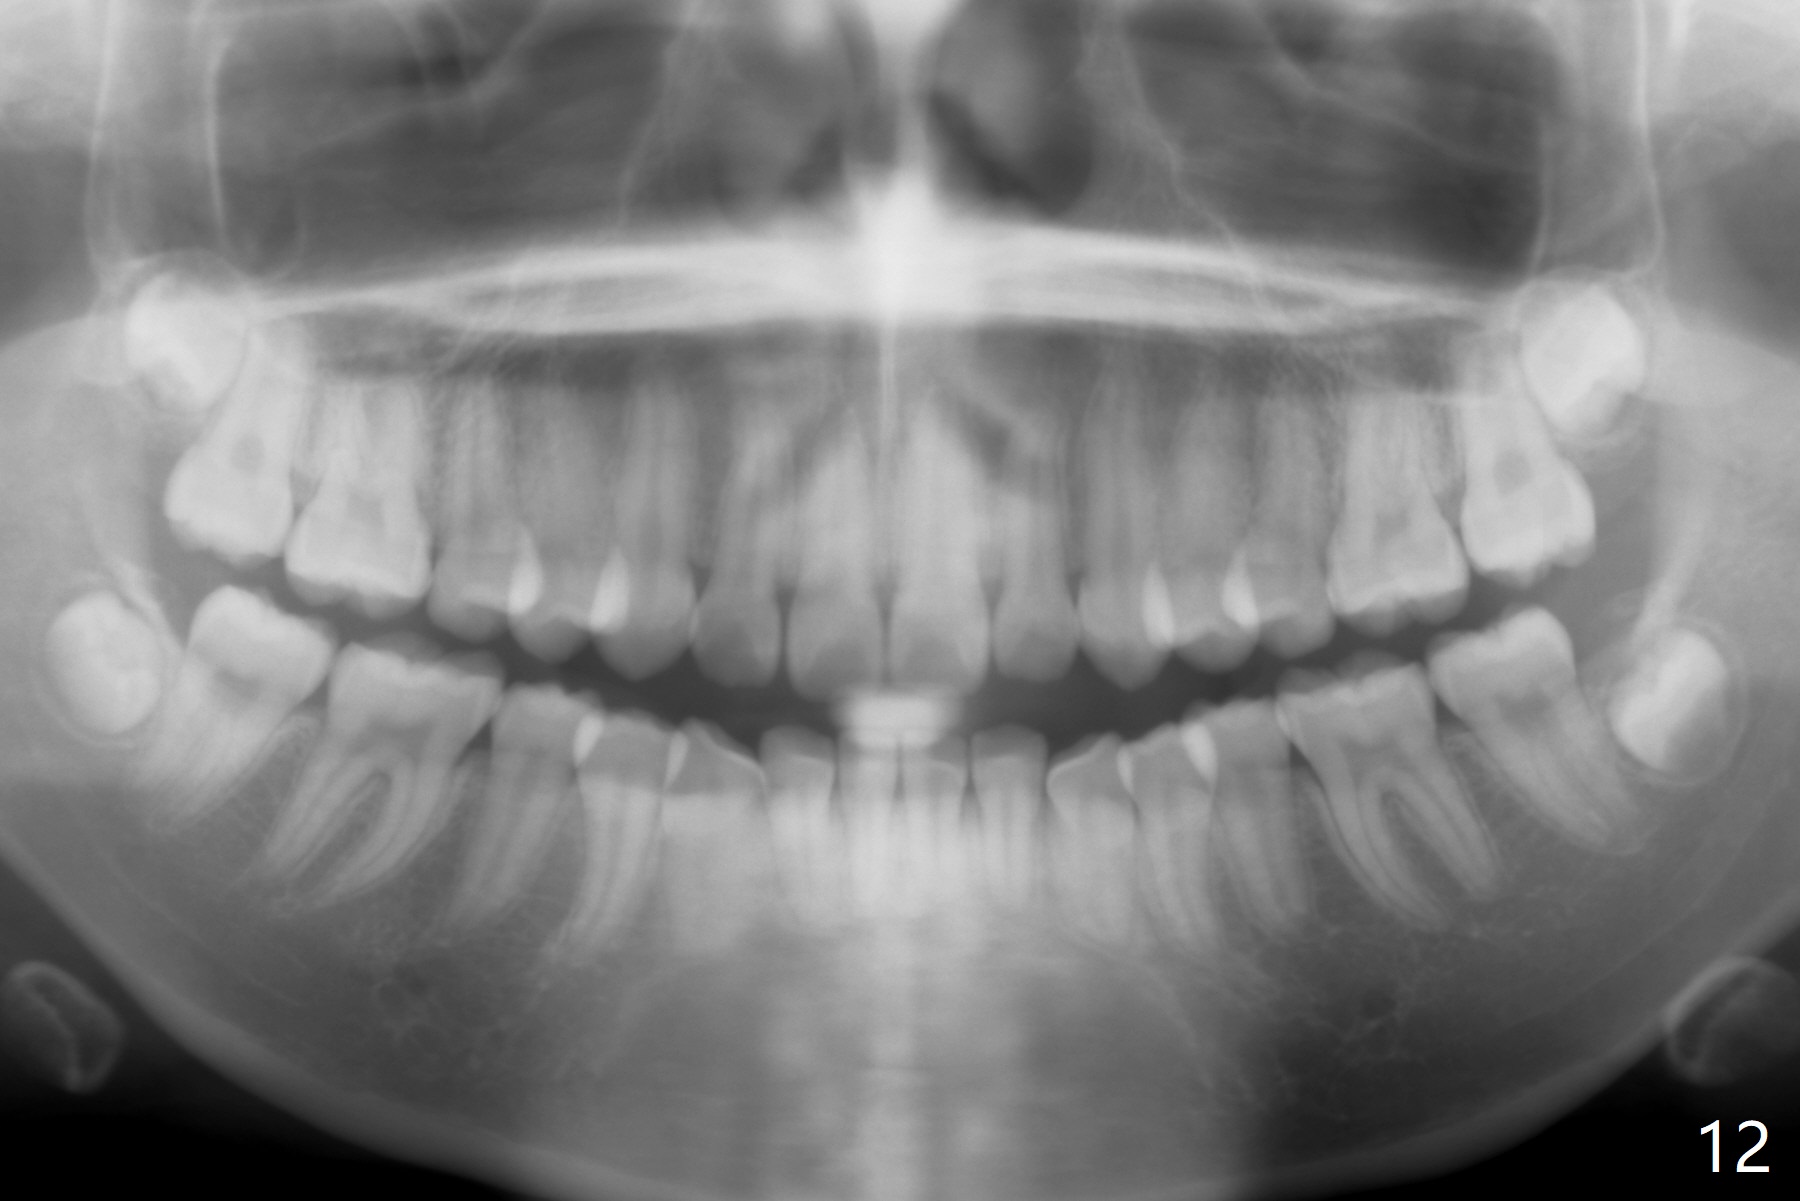

A 15-year-old woman has protrusive lips and retrusive chin (Fig.1-6). Canines and molars have Class I occlusion (Fig.7-9). With 4 bi extraction and 5-7 anchorage (Fig.10-12), 3s will be distalized after 16x16 wires, followed by posted wire retraction of 4 incisors.